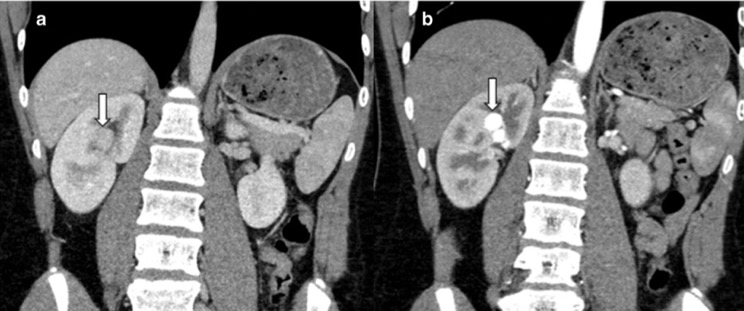

- Rein cicatriciel avec nodules de régénération